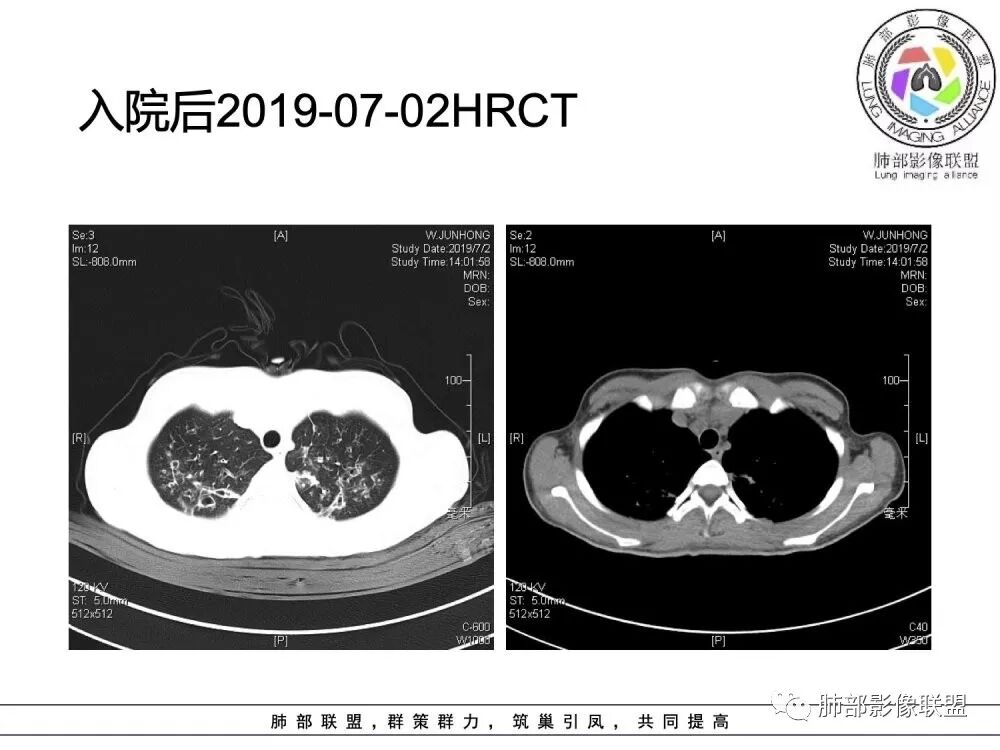

南边老师分析

这个病人15岁,病史10年,一直诊断支扩并感染,但是没提鼻窦病变;广泛支气管扩张,周围有伴随病灶,部分有钙化灶,肺气肿背景,首先是气道来源的病变,表现为:支气管壁增厚、支气管扩张、肺部感染;

(1)支气管壁增厚、支气管扩张

可广泛分布于两肺各叶,尤其是两肺上叶多见。支气管扩张主要是轻、中度柱状支气管扩张。支气管壁增厚既可发生于扩张的支气管,也可发生于非扩张的支气管,常为轻度增厚,管壁内外比较光滑。

(3)支气管黏液栓

由于黏液分泌物潴留在气管内形成,依据黏液存留的支气管走向不同而形态各异,多呈圆形、椭圆形、管状或尖端指向肺门的“V”形或“Y”形高密度阴影,密度均匀,边缘光滑锐利,CT值一般为15±10HU,但存留较久的黏液栓CT值可高达40~80HU,增强扫描无强化。

(4)薄壁含气囊腔

因支气管扩张、气肿性肺大泡及间质性气囊肿形成大小不一之囊腔,与支气管相关。